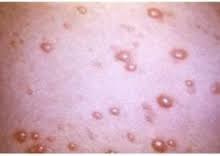

محققان به تازگی کشف کردند: سرخک حافظه سیستم ایمنی را از بین میبرد.

پژوهشگران کشف کرده اند که گرفتن سرخک حتی خطرناکتر از آن چیزی است که دکترها متوجه شدهاند، زیرا باعث میشود که قربانی به بیماریها ...